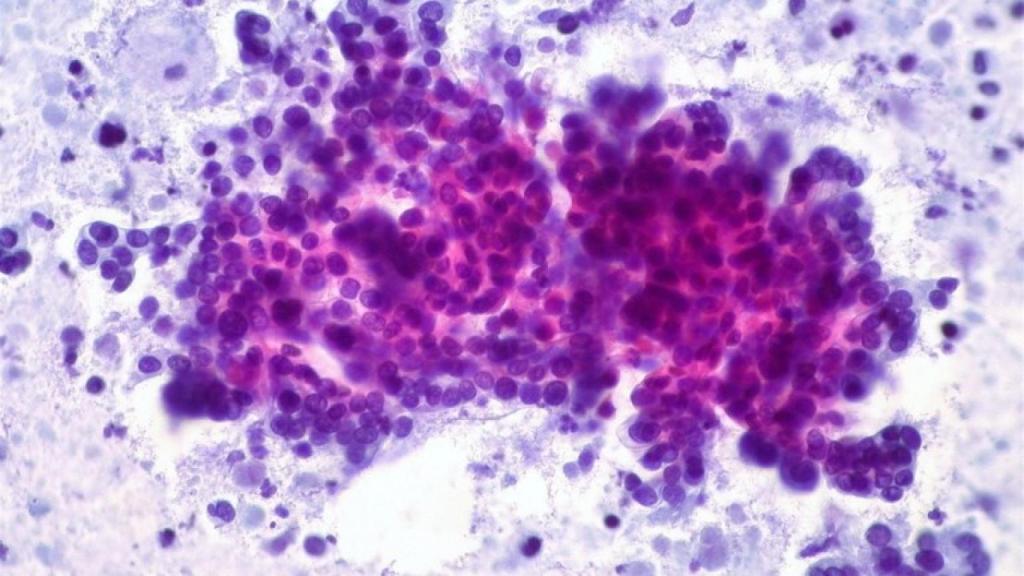

Sociedad LAS CÉLULAS TUMORALES UTILIZAN ELEVADOS NIVELES DE AZÚCAR PARA SEGUIR CRECIENDO

Científicos del Instituto Flamenco de Biotecnología y las universidades de Bruselas y Lovaina, en Bélgica, han aclarado por qué las células tumorales utilizan elevados niveles de azúcar para seguir creciendo, lo que se conoce como 'efecto Warburg', un hallazgo que puede tener un fuerte impacto en la dieta de los pacientes oncológicos.

Así se desprende de los resultados de un trabajo conjunto de investigación de más de 9 años que publica en su último número la revista 'Nature Communications', en el que vieron cómo los tumores convierten cantidades significativamente mayores de azúcar en alimento, en comparación con los tejidos sanos.

Este fenómeno ha sido ampliamente estudiado e incluso utilizado para detectar tumores cerebrales, entre otras aplicaciones. Pero hasta ahora no estaba claro si su efecto era simplemente un síntoma del cáncer, o una causa.